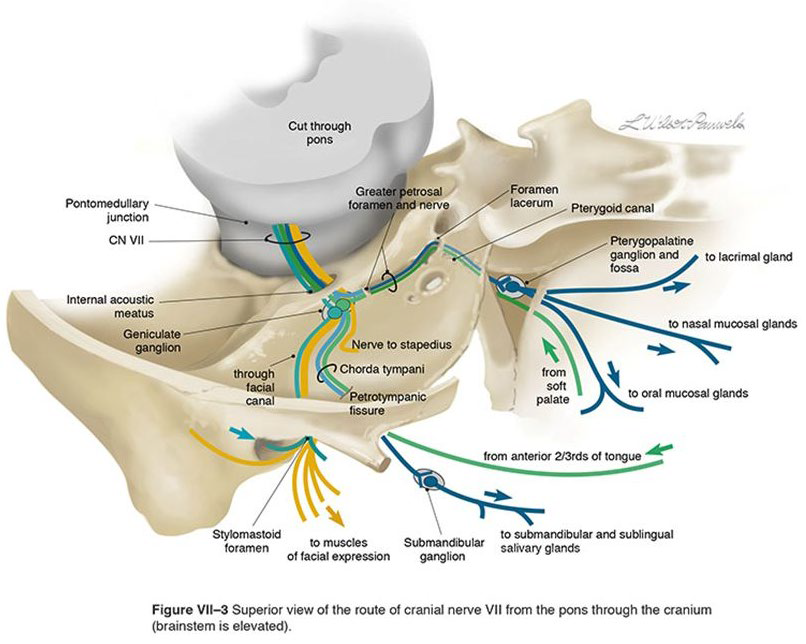

CN VII

-

Parotid plexus(支配表情肌)

- Temporal br.

- Zygomatic br.

- Buccal br.

- Marginal mandibular br.

- Cervical br.

-

Greater petrosal n.(Parasymphysis)

- Mucous g.

- Lacrimal g.

-

Stapedius n.

- 支配Stapedius m.

-

Chorda Tympanic n.(Parasymphysis)

- 支配前味覺

- Submandibular, Sublingual g.